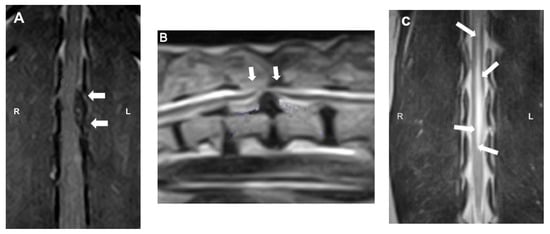

MRI (Figure 5) is currently considered the gold standard for the diagnosis of IVDD in both veterinary and human medicine. With a diagnostic sensitivity of over 98.5%, it provides detailed information on spinal cord compression and intramedullary lesions [41]. Characteristic findings include extradural compression of the spinal cord, visible as loss of the hyperintense signal of the nucleus pulposus on T2-weighted images, and the presence of a hypointense mass (extruded nucleus pulposus) on both T1- and T2-weighted images. The degree of spinal cord compression can be classified (on both CT and MRI) as mild (<25%), moderate (25–50%), or severe (>50%), according to the percentage reduction in spinal cord diameter. In addition, certain parameters observed on MRI images have been associated with unfavorable prognoses. Intramedullary T2 hyperintensity (more than six times the sagittal L2 length), T2 hypointensity, and CSF signal attenuation on HASTE/T2 * sequences have been variably associated with worse locomotor outcome and the development of PMM [43]. Despite its many advantages, MRI has certain limitations, such as high cost, long acquisition times, and lower availability compared to other imaging modalities [38,43].

Figure 5.

Magnetic resonance imaging (MRI) images: (A) dorsal T1W image showing the hypointense compressive material (arrows) at L2-3; (B) sagittal T2W image showing a severe ventral extradural compression in the ventral aspect of the vertebral canal at the intervertebral T13-L1 (arrows); (C) dorsal T2W image showing ill-defined intramedullary hyperintensity consistent with myelomalacia centered over L1–4 (arrows).